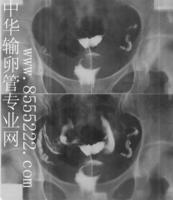

過X線這個特殊的射線把本不透明的,在腹壁外無法觀察到的輸卵管內腔通過注入造影劑作為對比劑在X光機上可清晰的直觀的通過肉眼看到子宮的大小,形態、結構、輪廓、位置和輸卵管走行等,尤其對輸卵管梗阻及其病因的診斷有重要價值,具體步驟可參考中華輸卵管專業網子宮輸卵管造影欄目.

輸卵管阻塞患者的排卵情況所用的子宮輸卵管造影檢查是一個影像學檢查,是通過導管向宮腔內注入造影劑而後經子宮腔造影劑流向輸卵管,而後通過X線下拍片把位於腹腔內的一個極細的肌性管道輸卵管顯示得非常的清楚。不僅能明確的顯示出輸卵管全程通暢情況,而且能非常明確的顯示出輸卵管阻塞的部位和性質,對於指導輸卵管疾病的治療起到了確定性的作用。它不僅能夠確診輸卵管梗阻部位,同時還能確定輸卵管梗阻性質及子宮大小形態有否有畸形,為檢查輸卵管是否通暢的首選檢查方法。